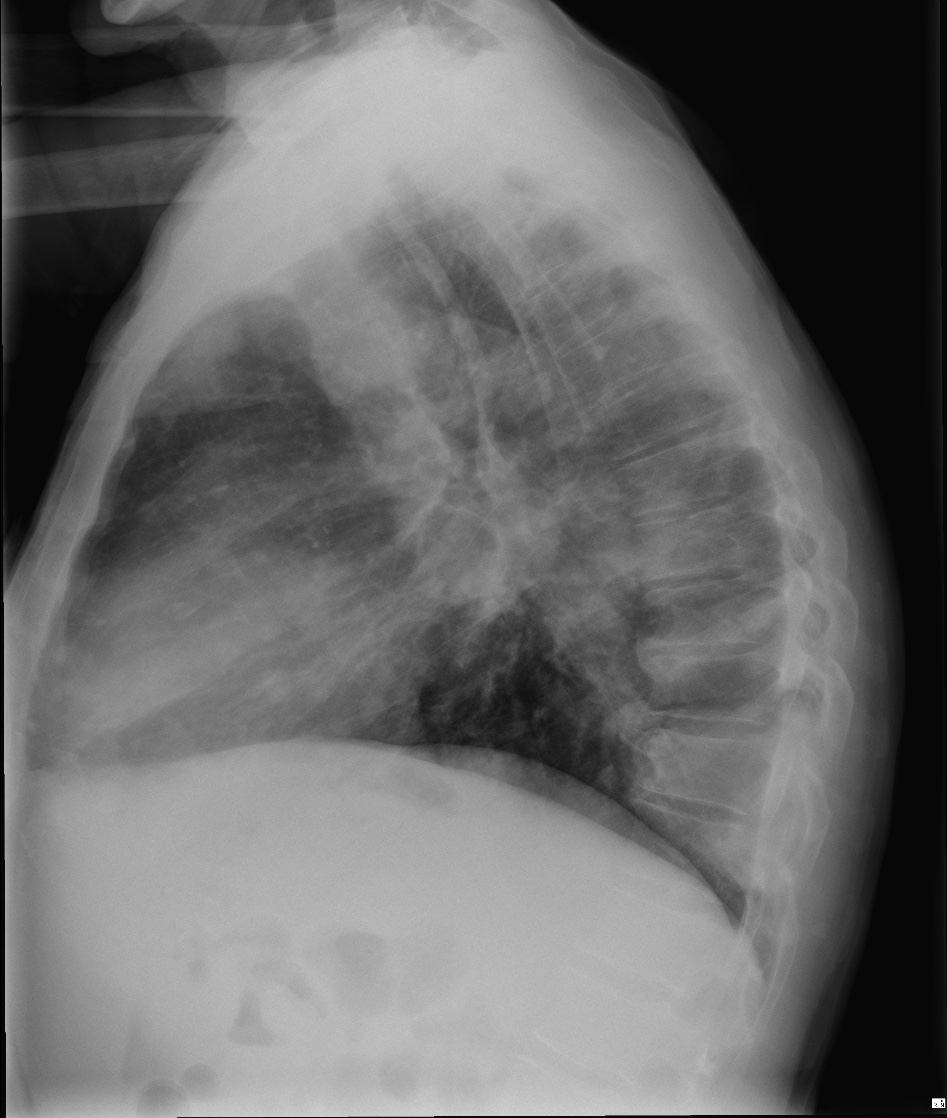

CASO: Febrícula y tos de 4 días de evolución.

Hallazgos:

- En la placa PA se observa una asimetría en los hilios pulmonares, el hilio izquierdo tiene una densidad aumentada.

- Tras examinar la placa lateral se observa un aumento de densidad en la columna que puede ser compatible con una condensación, es el signo de la desnificación vertebral.

SIGNO DE LA DENSIFICACIÓN VERTEBRAL: En la radiografía lateral normal, la densidad de la columna torácica tiende a disminuir desde la parte superior hasta el diafragma; la alteración de ese patrón por la presencia de una densidad superpuesta a la columna, indica la existencia de una consolidación pulmonar. Este signo adquiere especial valor cuando en la proyección posteroanterior la consolidación está oculta en el espacio retrocardíaco o en la base pulmonar.